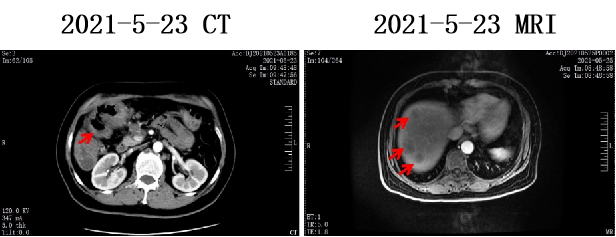

2021-5-17 外院肠镜示:结肠肝曲有新生物占据肠腔,肠腔狭窄,内镜无法通行。

肠镜活检病检提示:结肠腺癌。

我院病理会诊:腺癌 pMMR

KRAS/BRAF基因突变检测分析报告:KRAS、BRAF基因检测区域未检测到突变(野生型)。

2021-5-27 我院全身PET/CT示:横结肠近结肠肝曲肠壁增厚,代谢增高;肝内多发团块、结节灶,代谢增高;左颈部Ⅴ区、左锁骨上区、左侧膈肌脚内侧、肝门区、胰腺后方、横结肠周围及腹膜后区多发肿大淋巴结,代谢增高;上述考虑恶性病变,结肠癌伴肝脏、淋巴结转移。

PET/CT影像: